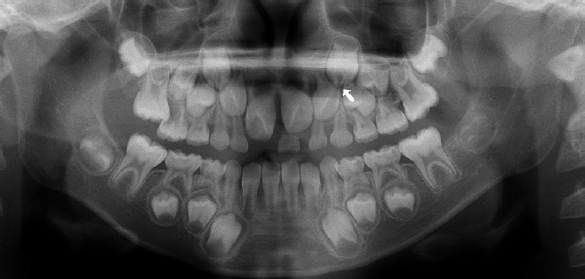

다발성 치아 맹출 장애로 본원에서 치료 중이던 13세 남아에서, 상악 좌측 견치와 제1소구치의 견인을 위한 외과적 노출술 시행 중 두 치아의 치관 교두정 부위에서 부분적 결손이 관찰되었다(Fig. 3C). 환아는 특이한 의학적 병력이 없었으며, 과거 촬영된 방사선 사진에서 해당 치아의 치관부에 방사선 투과상이 관찰되어 PEIR으로 진단하였다(Figs. 3A and B).외과적 노출 시 병소의 입구를 조심스럽게 제거한 결과, 상악 좌측 견치와 제1소구치 모두에서 치수와 개통된 광범위한 흡수성 병소가 확인되었다. 이에 두 치아에 직접 치수 복조술을 시행하였으며, calcium silicate 계열 복조재인 Biodentine (Septodont Corp., Paris, France)을 적용한 뒤, GI (Riva, SDI, Victoria, Australia)를 충전하였다(Figs. 4A and B).이후 11개월 경과 시 견인술을 통해 치아의 맹출이 이루어졌고, 임상 및 방사선학적 검사에서 이상 소견이 관찰되지 않았다(Figs. 4C and D). GI 수복물을 제거하고 접착제(Scotchbond Universal Adhesive, Solventum, St. Paul, MN, USA)를 도포한 후 복합레진(Filtek Z250 Universal Restorative A2, Solventum, St. Paul, MN, USA)을 이용한 영구 수복을 시행하였다. 환아는 이후 장기간 본원에 내원하여 정기적인 경과 관찰을 받았으며, 9년 간의 추적관찰 기간 동안 별다른 증상은 발생하지 않았으며 치관부에 잔존하는 치관부 방사선 투과상은 변화 없이 유지되었다. (Figs. 5A-C). 9년 후 임상검사 상 치관부의 변색 및 방사선 사진 상 삼차 상아질 형성이 관찰되었으며 추가적인 치료는 시행하지 않았다(Figs. 5D and E).- 증례 3

Figure 3.

Preoperative radiographic images and intraoral photographs. A. Panoramic radiograph. B. Cone-beam computed tomography image. C. A coronal defect is identified upon flap reflection.

Figure 6.

Panoramic radiograph taken at 7 years old. A radiolucent area is observed in the developing crown of tooth #23.